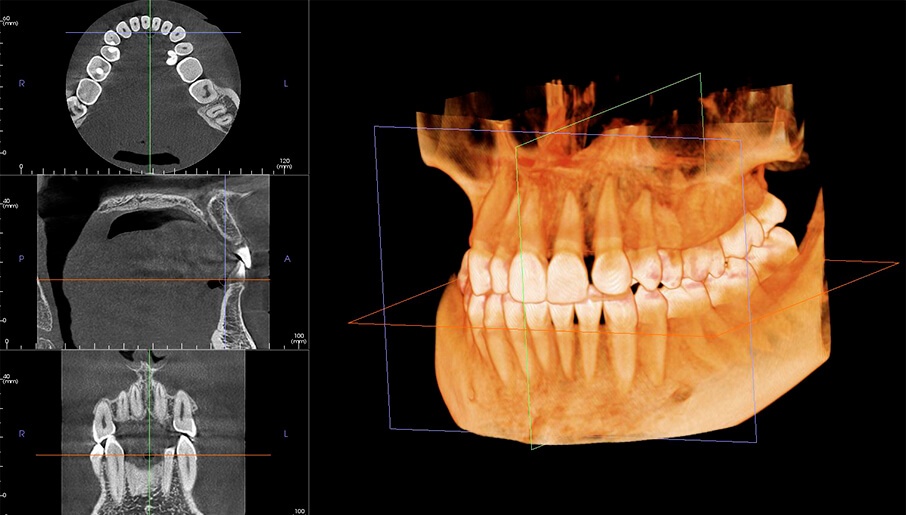

Компьютерная томография (КТ) – это мощный инструмент визуализации, который позволяет стоматологам увидеть структуру челюстно-лицевой области в трех измерениях․ Однако анализ КТ-снимков – это сложный и трудоемкий процесс, требующий от врача высокой квалификации и большого опыта․ Здесь на помощь приходит ИИ․

ИИ-алгоритмы способны анализировать КТ-снимки намного быстрее и точнее, чем человек․ Они могут автоматически обнаруживать патологии, такие как кариес, воспалительные процессы, трещины и переломы костей․ Более того, ИИ может даже предсказать риск развития определенных заболеваний на основе анализа КТ-снимков․ Например, он может оценить плотность костной ткани и спрогнозировать вероятность отторжения имплантата․

Представьте себе, насколько это упрощает работу врача! Вместо того, чтобы часами изучать снимки, он может получить готовый отчет с подробным анализом, выделить время на общение с пациентом и разработку оптимального плана лечения․ Это не только экономит время, но и снижает вероятность ошибок, что, безусловно, положительно сказывается на качестве лечения․

Например, мы используем ИИ для анализа КТ-снимков при планировании имплантации․ Раньше на анализ одного снимка у нас уходило около часа, а сейчас ИИ делает это за несколько минут․ Это не только экономит наше время, но и позволяет нам выявить патологии, которые мы могли бы пропустить при ручном анализе․